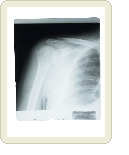

어깨 결림과 예방법

신경, 근육, 힘줄 등에 원인으로 어깨결림 현상이 발생하게 되면 Rehabilitation(사회복귀요법) 치료훈련을 받으면 치료가 가능하지만 내장질환이 원인이면 방산통(放散痛)을 일으키거나 움직임이 제한되기도 한다.

예를 들어 심장질병, 종양, 경추(頸椎)염증성, 변형성질환이 원인으로 어깨에 결림증상이 나타나는 경우도 있다.

다른 질병과의 합병증을 감안하면서 발생원인을 찾는 일도 중요하다. 왜냐하면 등뼈가 굽어져서 어깨에 영향을 주는 경우도 있기 때문이다.

자율신경실조증(自律神經失調症)을 일으켜 발한이상, 오심구토(惡心嘔吐), 귀 울림 등을 호소하는 사람도 있는데 그럴 때에는 전문의사와 상담하여 질환의 원인을 찾는 것이 중요하다.

【방산통】한곳에서 일어난 통증이 넓은 부분으로 퍼져가듯이 느끼는 통증.